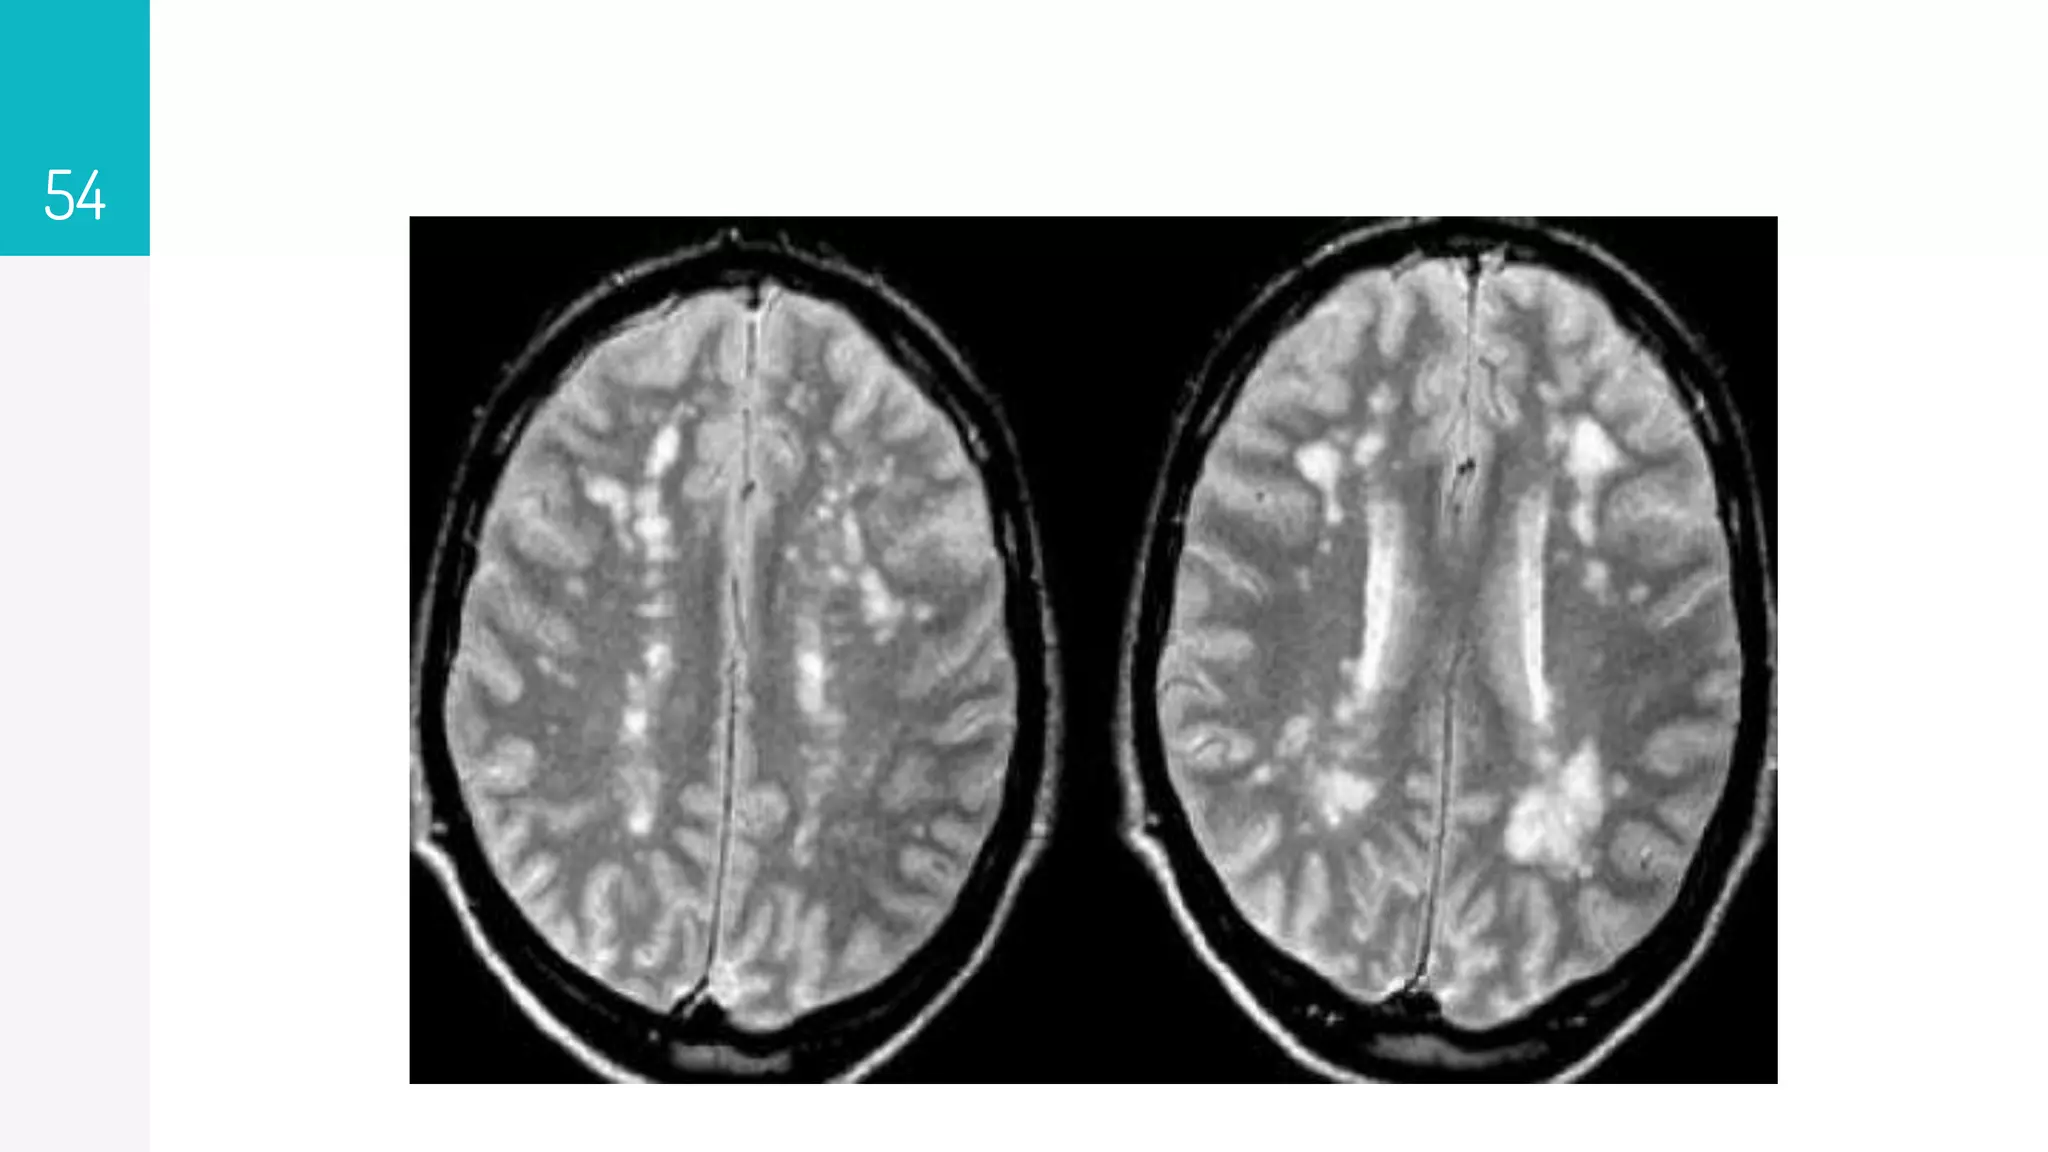

▹ MRI of the brain is the most accurate test to diagnose MS,

reaching a sensitivity of 85 to 95% in symptomatic

persons.

▹ Increased T2 and decreased T1 intensity represent the

increased water content of demyelinated plaques in the

cerebrum and spine.

▹ Enhancement of lesions with gadolinium indicates active

MS lesions that may enhance for up to 2 to 6 weeks after

an exacerbation

54